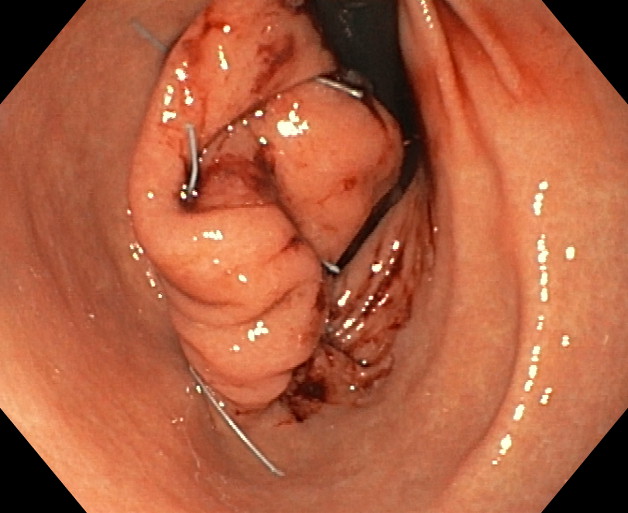

ENDOMANGA

La endomanga es una técnica quirúrgica (gastroplastia) mínimamente invasiva que se realiza por vía endoscópica, es decir, a través de la boca y que permite modificar de forma definitiva la forma del estómago, acortándolo e igualmente dándole un aspecto pseudo-tubular. No se realizan incisiones externas y, por tanto, no hay cicatrices. Está indicada como primera opción para pacientes con obesidad moderada (IMC entre 30 y 40), o en caso de obesidades severas (IMC superior a 40) que no desean enfrentarse a técnicas quirúrgicas de mayor envergadura (cirugía bariátrica) para reducción del peso.

El objetivo de la endomanga gástrica es reducir el estómago, limitando la capacidad de éste. Como consecuencia de ello, el paciente presenta una mayor saciedad ingiriendo una menor cantidad de alimentos y le es más fácil adaptarse a nuevos hábitos saludables duraderos.

La gastroplastia endoscópica mediante la técnica endomanga se realiza por el gastroscopia, bajo anestesia general y dura aproximadamente entre 25 y 35 minutos. Mediante la endoscopia se realizan unos 18 pliegues definitivos a lo largo de todo el cuerpo gástrico, reduciendo de manera importante su capacidad de apertura, acortándolo y estrechándolo. Gracias a esta reducción los pacientes disminuyen la sensación de hambre.

Los pacientes, tras la intervención, permanecen ingresados en hospitalización por lo general no más de 16-24 horas, ya que se trata de una intervención mínimamente invasiva y de bajo riesgo, por lo que la tolerancia suele ser excelente. La incorporación a su vida cotidiana es rápida, en 2-3 días por lo general. El postoperatorio es muy bueno en general, con dolor o molestias abdominales controlables con medicación y que no suelen ir más allá de los 2-3 primeros días. A los pocos días de la operación se realiza un control médico para comprobar que el paciente evoluciona de forma correcta y, a partir de ahí, se comienza el programa de seguimiento.

Los pacientes sometidos a la técnica pierden peso de una manera muy fisiológica y progresiva desde el mismo momento de la intervención. Además, tras la intervención el paciente comenzará un programa de reeducación alimentaria y un seguimiento médico, nutricional y psicológico para adquirir unos hábitos saludables y que le permitan mantener el peso a largo plazo. El programa de seguimiento lo establecemos en 18 meses con visitas regladas pero abiertas a las necesidades del paciente.